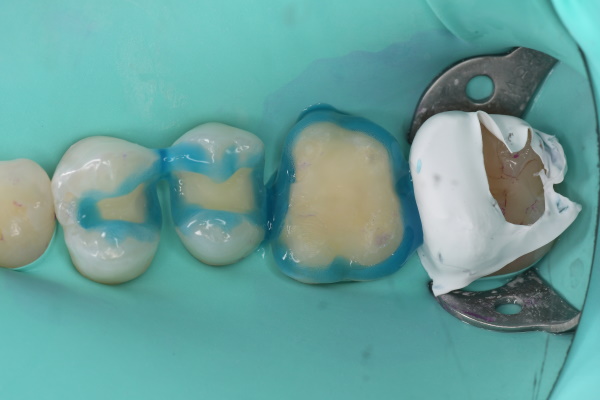

セラミック治療の治療例です。虫歯になった歯を、見た目もきれいに治したいとのご希望で来院されました。当院にて、3本同時にセラミックによる修復を実施しました。染め出しにより取り残しや汚れを確認し、プラークなどを除去したうえでセラミックを装着しています。オキシガードは、過酸化物と還元剤による化学重合反応により、歯科接着用レジンセメント表面の未重合層を硬化させる材料です。さらに、未重合層を空気から遮断することで確実な硬化を促します。接着効率をあげるためにラバーダムを使用し治療を行っております。

セット前の染出し

エッチング後